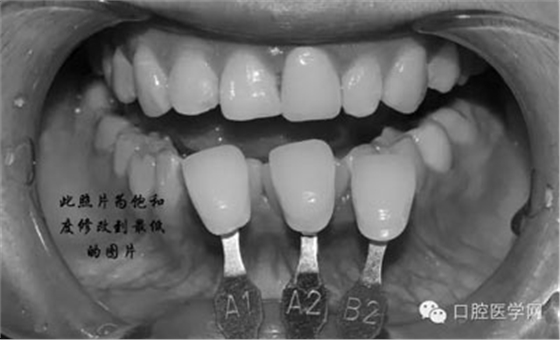

將比色照飽和度調(diào)到最低有助于牙齒明度的選擇

7、術(shù)后照飽和度調(diào)到最低與最高,觀察牙齒修復(fù)后的明度及飽和度